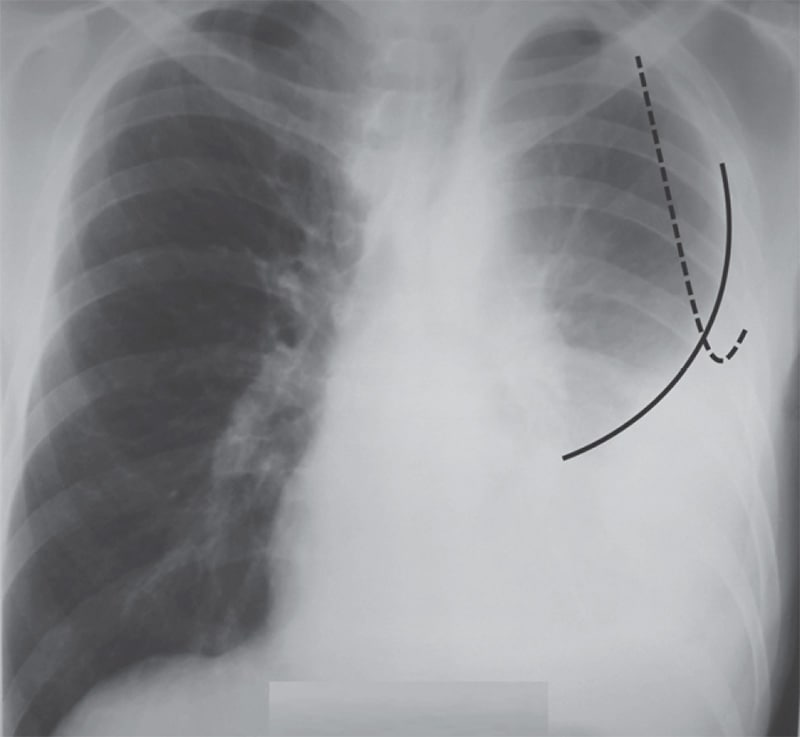

Диагностика плеврального выпота: что нужно знать